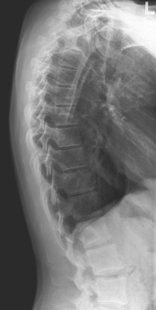

• Recumbent, support under head, lateral with hips and knees flexed, arms raised and elbows flexed. Shield radiosensitive tissues.

• Align and center midaxillary plane to centerline

• Top of IR 1.5″ (3 cm) above shoulders; no rotation

• Supports should be placed under lower back as needed to straighten and align spine near parallel to tabletop. (A slight natural curvature corresponding to divergent rays is helpful.)